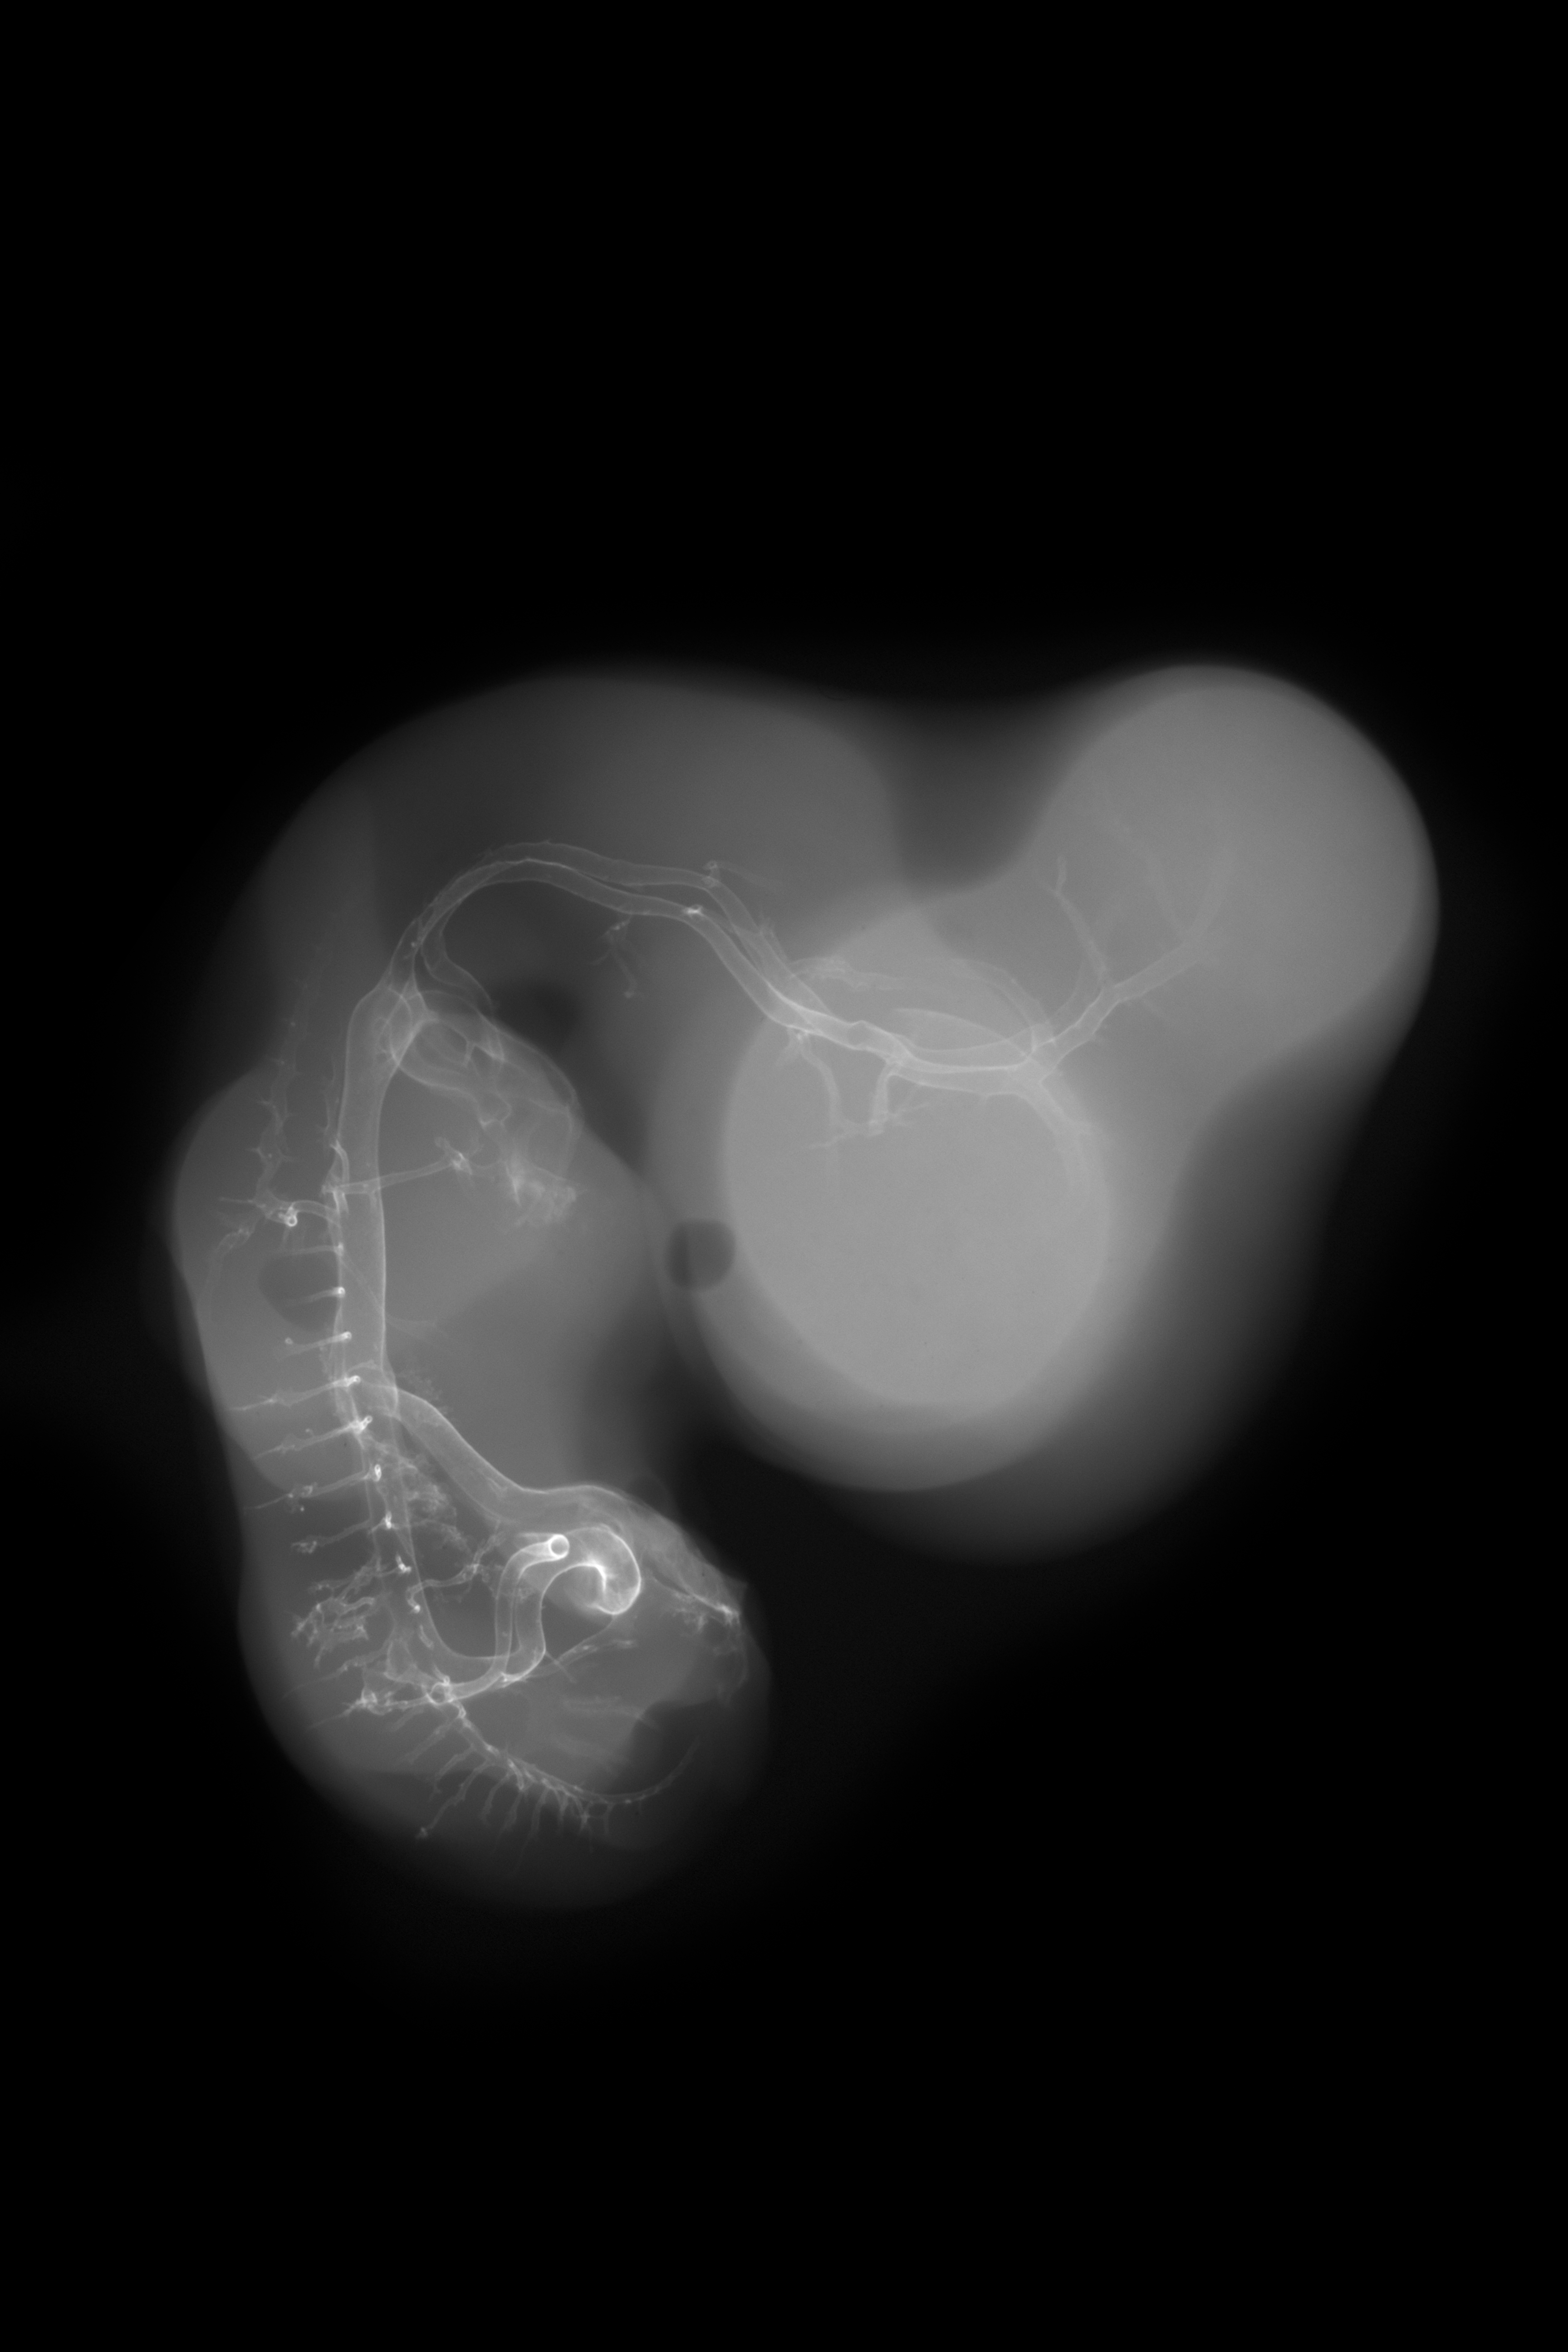

Chick Embryo Microangiography

Hamburger-Hamilton (HH) Stage 28 (approx. 5.5 - 6 days)

X-Ray Micrographs